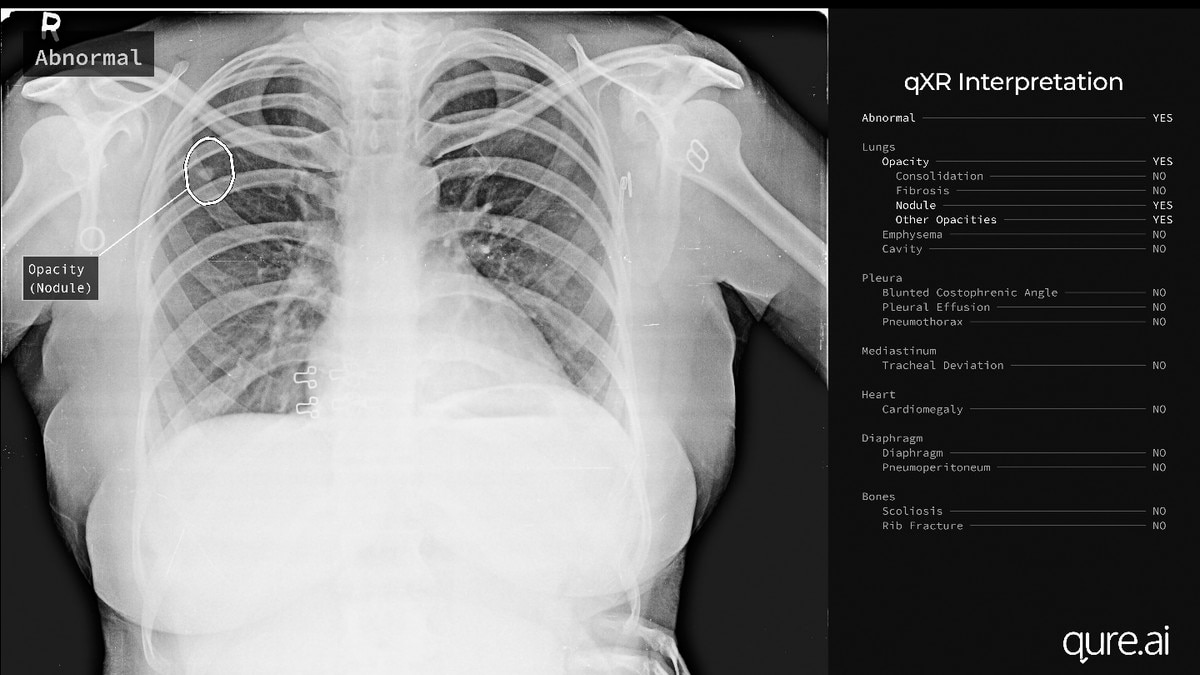

कोरोना वायरस के लक्षणों को महज 30 सेकेंड में बता देती है ये टेक्नोलॉजी

कोरोना को लेकर पूरी दुनिया में दहशत फैली हुई है. वैक्सीन आने का इंतजार किया जा रहा है. बड़ी चुनौती कोरोना की जांच करना भी है. ऐसे में राहत की खबर ये है कि झारखंड के कोडरमा निवासी एक युवक ने ऐसी आर्टिफिशियल इंटेलिजेंस (एआई) टेक्नोलॉजी खोजी है, जिससे महज 30 सेकेंड में छाती के एक्स-रे के सहारे कोरोना के लक्षणों का पता लगाया जा सकता है. (इनपुट- मृत्युंजय श्रीवास्तव)

ये टेक्नोलॉजी टीबी के लक्षणों को पता करने के लिए तैयार की गई थी, लेकिन कोरोना को लेकर इसे और भी विकसित किया गया. कोडरमा जिले के झुमरीतिलैया के अड्डी बंगला रोड निवासी 28 वर्षीय अंकित मोदी मुंबई में एक कंपनी के सह संस्थापक हैं. उनकी कपंनी ने एक आर्टिफिशियल इंटेलिजेंस टेक्नोलॉजी खोजी है. यह मात्र एक मिनट में ब्रेन का सिटी स्कैन कर रिपोर्ट देने में सक्षम है.

खास बात ये है कि अंकित और उसके सहयोगियों द्वारा बनाये गये इस साॅफ्टवेयर में रेडियोलॉजिस्ट की जरूरत नहीं पड़ती है. इस साॅफ्टवेयर का प्रयोग अमेरिका, इंग्लैंड, फ्रांस, इटली समेत दुनिया के 20 से भी अधिक देशों में किया जा रहा है. अंकित के पिता जितेंद्र कुमार अरुण व्यवसायी हैं.  अंकित और उनके सहयोगियों द्वारा तैयार किये गये इस सॉफ्टवेयर की कहानी पिछले दिनों अमेरिका के प्रसिद्ध अखबार न्यूयॉर्क टाइम्स में प्रकाशित हुई थी.

जिन हॉस्पिटलों में एक्स-रे की रिपोर्ट आने में पहले कई दिन और सप्ताह लग जाते थे, अब वहां इस सॉफ्टेवयर की मदद से वही रिपोर्ट मिनटों में बन रही है. जो डॉक्टर पहले दिन में 25 से 30 एक्स-रे देख पाते थे, अब वो एक दिन में 100 से भी ज्यादा एक्स-रे देख पा रहे हैं. कई ऐसे भी केस सामने आए हैं, जहां बीमारी के बहुत ही सूक्ष्म लक्षण एक्स-रे में मौजूद थे, जो कि आंखों से पकड़ पाना मुश्किल होता था, ऐसे मामलों को डॉक्टर इस टेक्नोलॉजी की मदद से आसानी से पकड़ पाए हैं.

अंकित मोदी ने बताया कि जिन सुदूर गांवों और कस्बों में एक्स-रे की सुविधा तो है पर उन्हें देखने वाले रेडियोलाजिस्ट की कमी है, वहां ये तकनीकि रेडियोलाजिस्ट की कमी को पूरा करने में बेहद कारगर सिद्ध हुई है. उन्होंने बताया कि इसकी एक बानगी झारखण्ड में सिमडेगा के शान्तिभवन मेडिकल सेंटर में देखने को मिलती है.